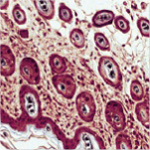

The OSR Mouse Clinic (OMC) stems from the above rationale and is the follow-up and consolidation of a Regione Lombardia-funded project (EMDM), which aimed at the establishment and implementation of a large, dedicated facility (the European Mouse Disease Models Center) whose goal is the development and functional assessment of mouse disease models, both for the dissection of the underlying pathogenic mechanisms and for the screening and validation of innovative diagnostic and therapeutic procedures. OMC has been conceived to face the challenges posed by the development of mouse models of disease that are more reliable and display higher predictive value for the corresponding human condition. OMC has developed and standardized a coordinate set of activities, including the creation of a non invasive imaging facility, based on the acquisition of dedicated equipment (7-Tesla small bore MRI; micro-CT scanner; micro-US scanner; optical imaging scanner; micro-PET), the creation of a comparative pathology Unit and the implementation of a dedicated area for the use of mouse pathogens. OMC also aims at potentiating the existing Conditional Mutagenesis Facility by implementing novel approaches to attain tissue-, stage- and site-specific transgene expression in mouse mutant strains, mainly through lentiviral vector-mediated transduction of blastocysts.

A major asset of the OMC platform is the tight integration of preclinical scientists with physicians, who work side by side to comparatively assess pathogenic, diagnostic and therapeutic issues raised in patients with the mouse model counterpart.